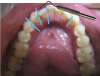

Fig 2. Candidates for hybrid teledentistry include patients with minor (Fig 2), moderate (Fig 3), and advanced crowding (Fig 4).

FIgure 2

Fig 3. Candidates for hybrid teledentistry include patients with minor (Fig 2), moderate (Fig 3), and advanced crowding (Fig 4).

Figure 3

Fig 4. Candidates for hybrid teledentistry include patients with minor (Fig 2), moderate (Fig 3), and advanced crowding (Fig 4).

Figure 4